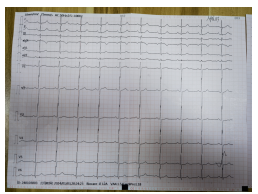

1月4日15:45左右,罗大爷再次出现胸痛,予以“硝酸甘油”舌下含服后无明显缓解,16:00复查心电图,考虑急性前壁ST段抬高型心肌梗塞超急性期,值班医生蔡波副主任医师查看患者后,建议立即行急诊冠状动脉造影及必要时支架植入术,尽早手术才能拯救更多的心肌,患者家属商议后同意并签署心导管诊疗同意书。